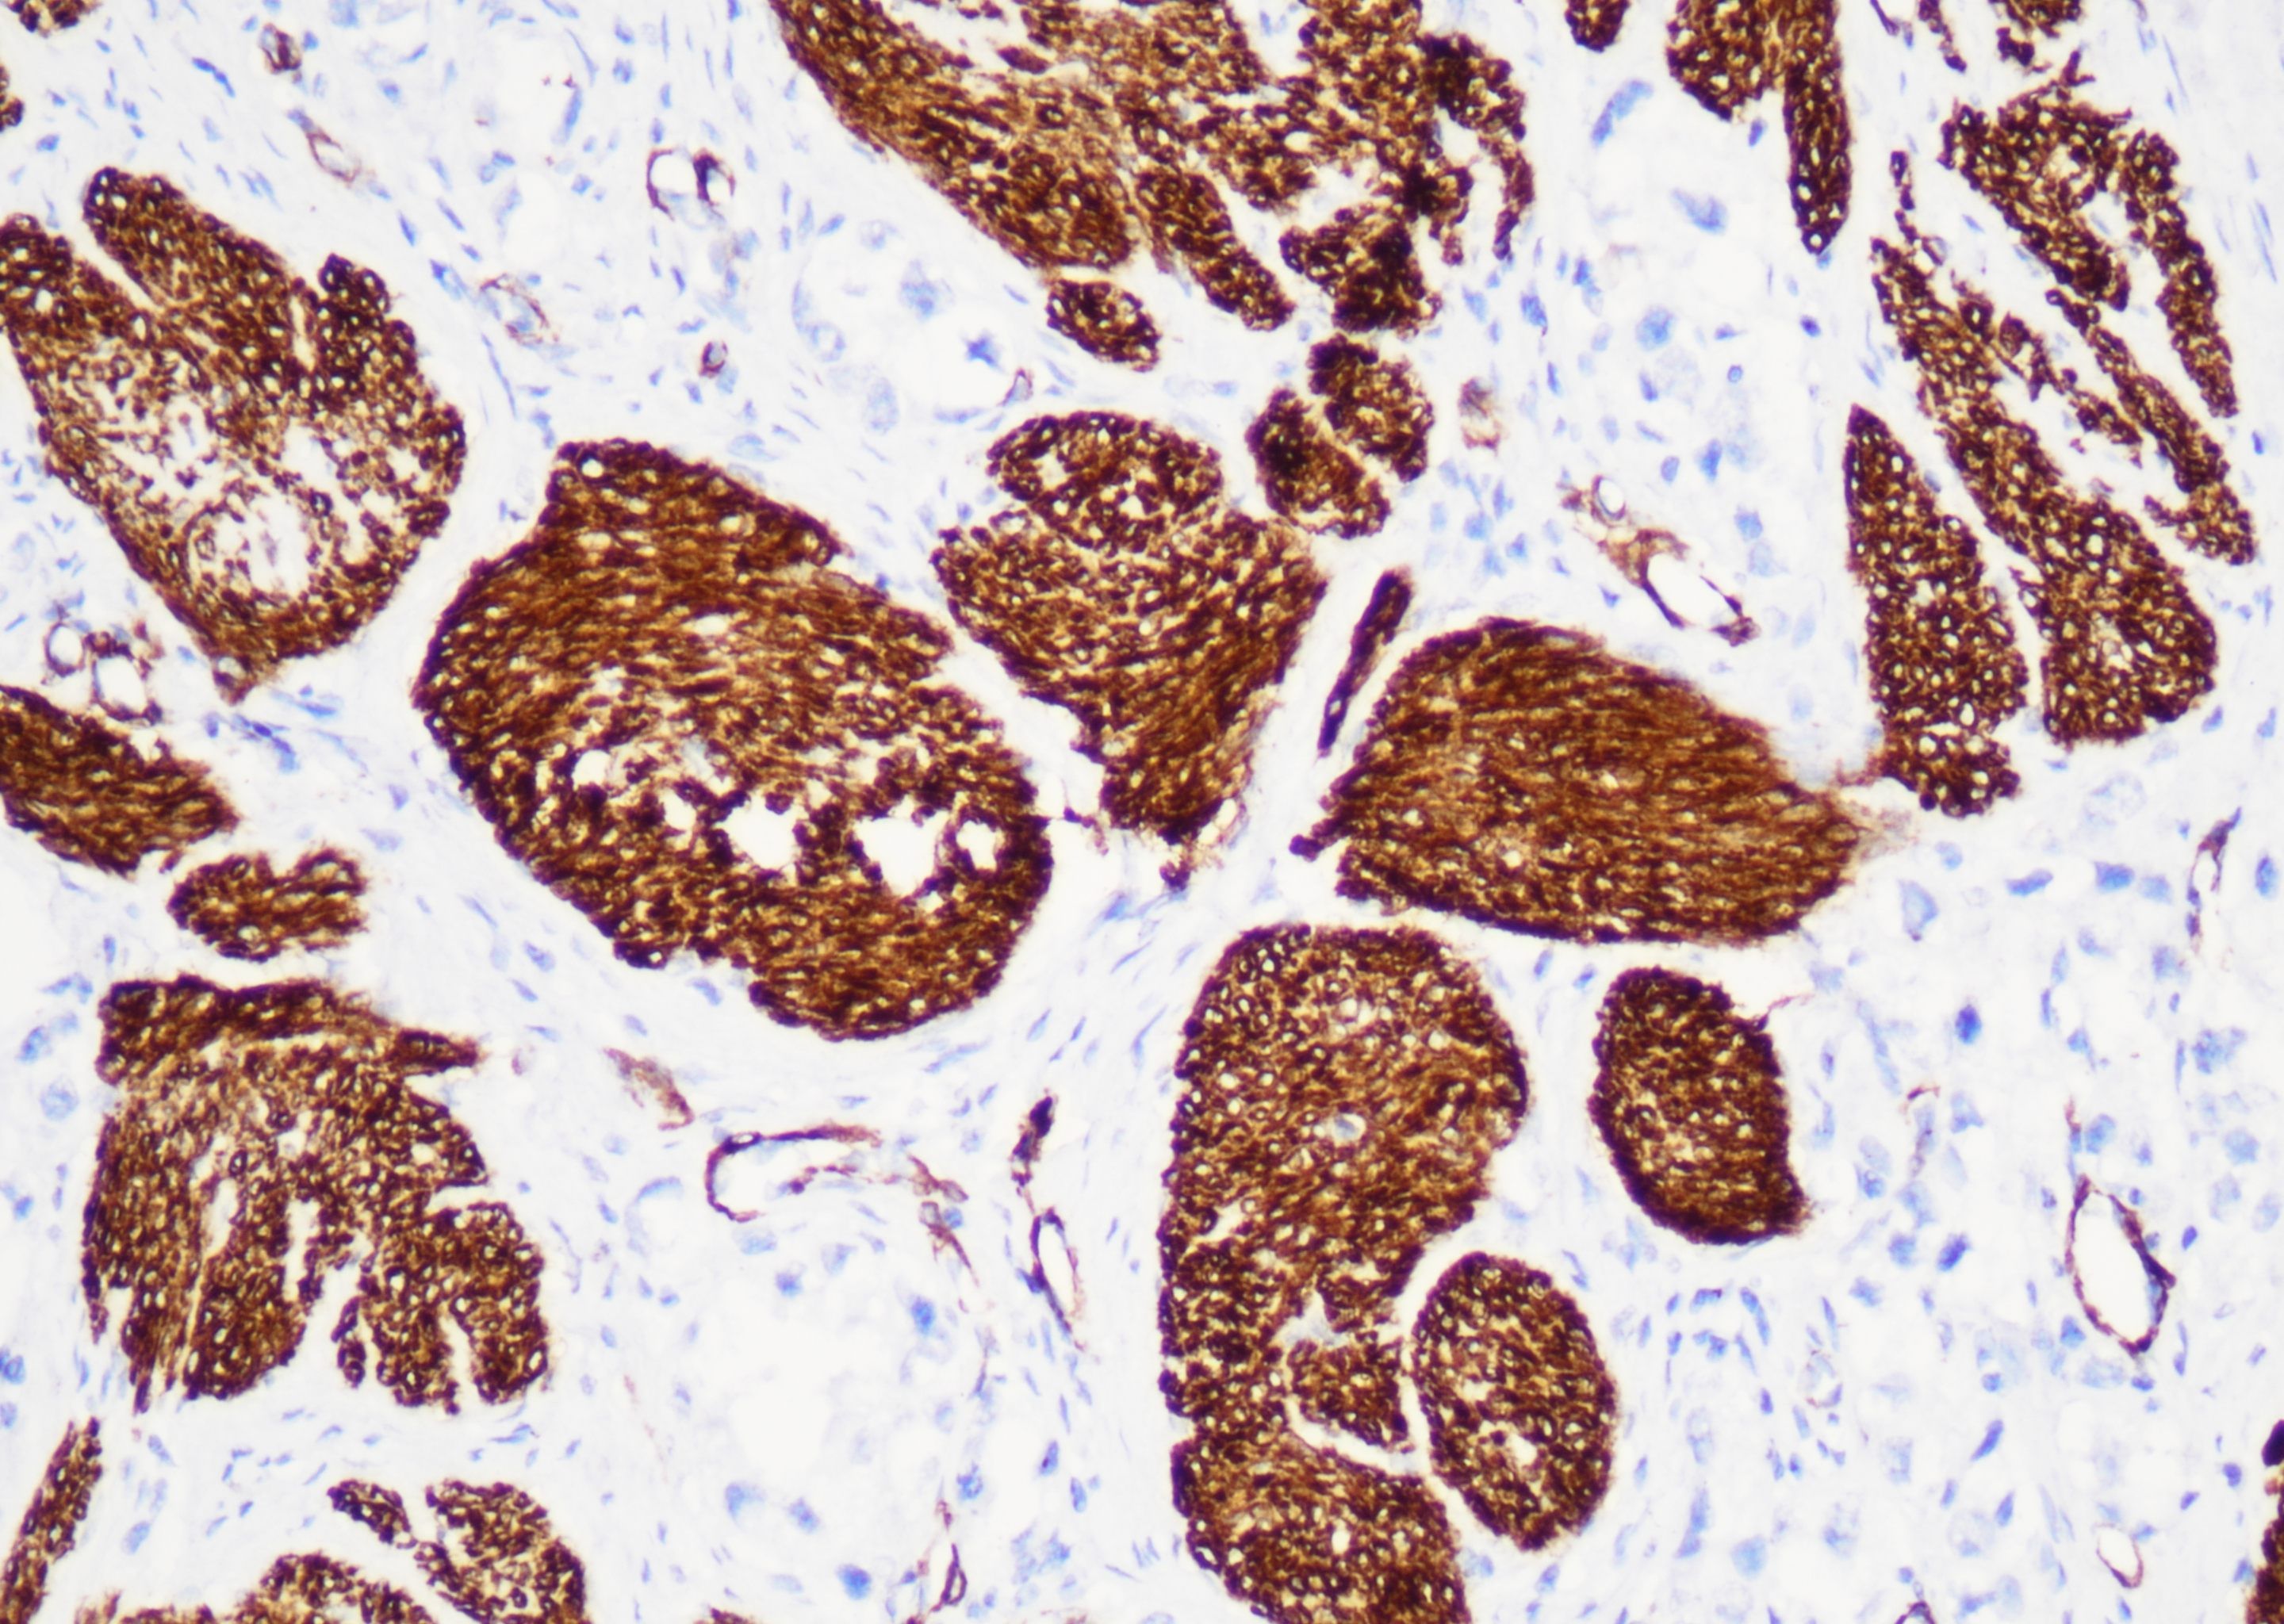

Bcl-2

bcl-2是细胞凋亡蛋白家族成员之一,是一种分子量为25kDa 的线粒体内膜蛋白,抑制细胞凋亡,在组织 内广泛存在。其主要表达于套区的小B淋巴细胞和部分T细胞、胸腺髓质细胞和正常乳腺导管上皮细胞。原发性乳腺癌通常bcl-2表达阳性,其表达与p53 表达负相关,bcl-2阳性者预后较好。bcl-2可用于滤泡性淋巴瘤与 反应性淋巴滤泡增生、皮肤纤维瘤,纤维瘤病与孤立性纤维性肿瘤,隆突性皮肤纤维肉瘤、单核样B细胞增生与 边缘区淋巴瘤的鉴别诊断。